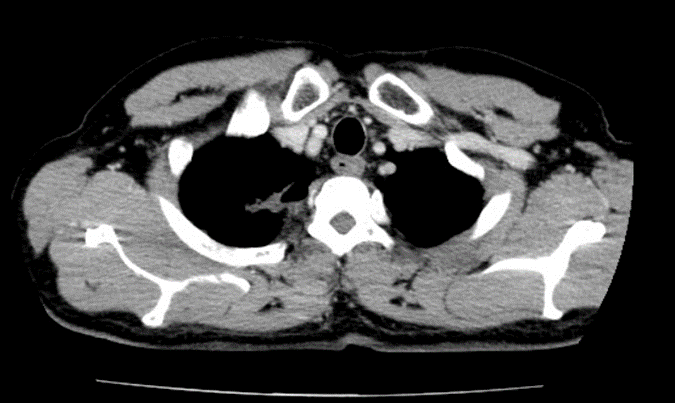

– Chụp cắt lớp vi tính lồng ngực:

Hình 1: Hình ảnh chụp cắt lớp vi tính lồng ngực: Hình ảnh khối u thùy trên phổi phải kích thước 5x6cm, hạch trung thất, rải rác tổn thương thứ phát hai phổi (Mũi tên màu đỏ).